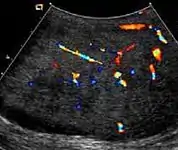

At ultrasound, the findings of acute epididymitis include an enlarged hypoechoic or hyperechoic (presumably secondary to hemorrhage) epididymis [Fig. 20a]. Other signs of inflammation such as increased vascularity, reactive hydrocele, pyocele and scrotal wall thickening may also be present. Testicular involvement is confirmed by the presence of testicular enlargement and an inhomogeneous echotexture. Hypervascularity on color Doppler images [Fig. 20b] is a well-established diagnostic criterion and may be the only imaging finding of epididymo-orchitis in some men.

Doppler ultrasound of epididymitis, seen as a substantial increase in blood flow in the left epididymis (top image), while it is normal in the right (bottom image). The thickness of the epididymis (between yellow crosses) is only slightly increased (7 mm).